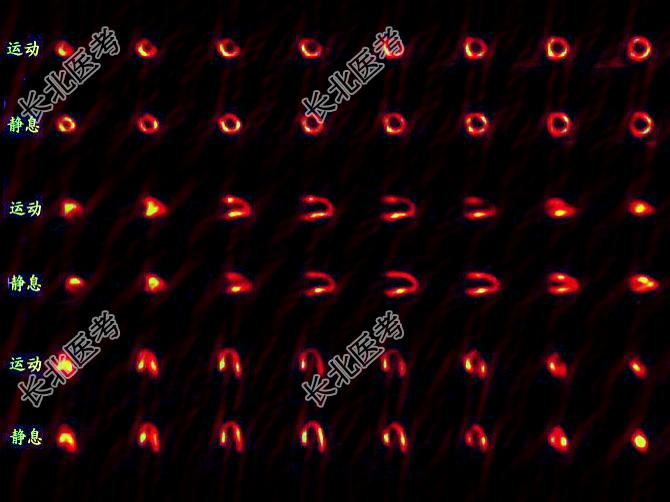

多项选择题一患者的心肌灌注显像对比如图,正确的诊断是 ( )

A、左心室前壁可逆性缺血

B、PTCA疗效显著

C、PTCA无明显疗效

D、术后再狭窄